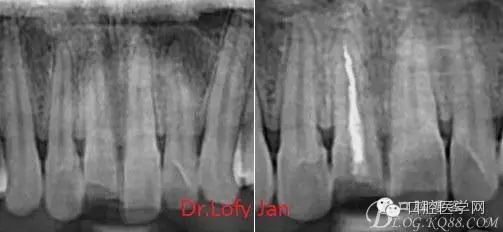

《數(shù)字化根尖片、曲面斷層片、CBCT測量牙齒長度準(zhǔn)確性的比較研究》文中顯示:平行投照數(shù)字化根尖片影像長度和牙齒實際長度之間無顯著性差異(P0.05);數(shù)字化曲面斷層片影像長度和牙齒實際長度之間有顯著性差異(P0.05),平均失真率為17.05%。CBCT冠狀面測量結(jié)果中除上頜前磨牙區(qū)、下頜前磨牙區(qū)與真實長度差異無統(tǒng)計學(xué)意義(P0.05)外,其余6個分區(qū)差異均有統(tǒng)計學(xué)意義(P0.05);矢狀面測量結(jié)果中上頜磨牙區(qū)、下頜磨牙區(qū)、下頜前磨牙區(qū)、下頜尖牙區(qū)、下頜前牙區(qū)與真實長度比較差異均有統(tǒng)計學(xué)意義(P0.05)。結(jié)論平行投照數(shù)字化根尖片較曲面斷層片和CBCT能更加精確地反映牙齒的真實長度。

病例分析:曲面斷層片在x線輔助診斷與檢查中目前大多數(shù)文獻(xiàn)和著作都建議只能作為初診拍片檢查手段,不能作為終末疾病的確診與手術(shù)療效的評價指標(biāo),臨床大部分中小型門診都因為設(shè)備不齊全導(dǎo)致信息偏差很大。